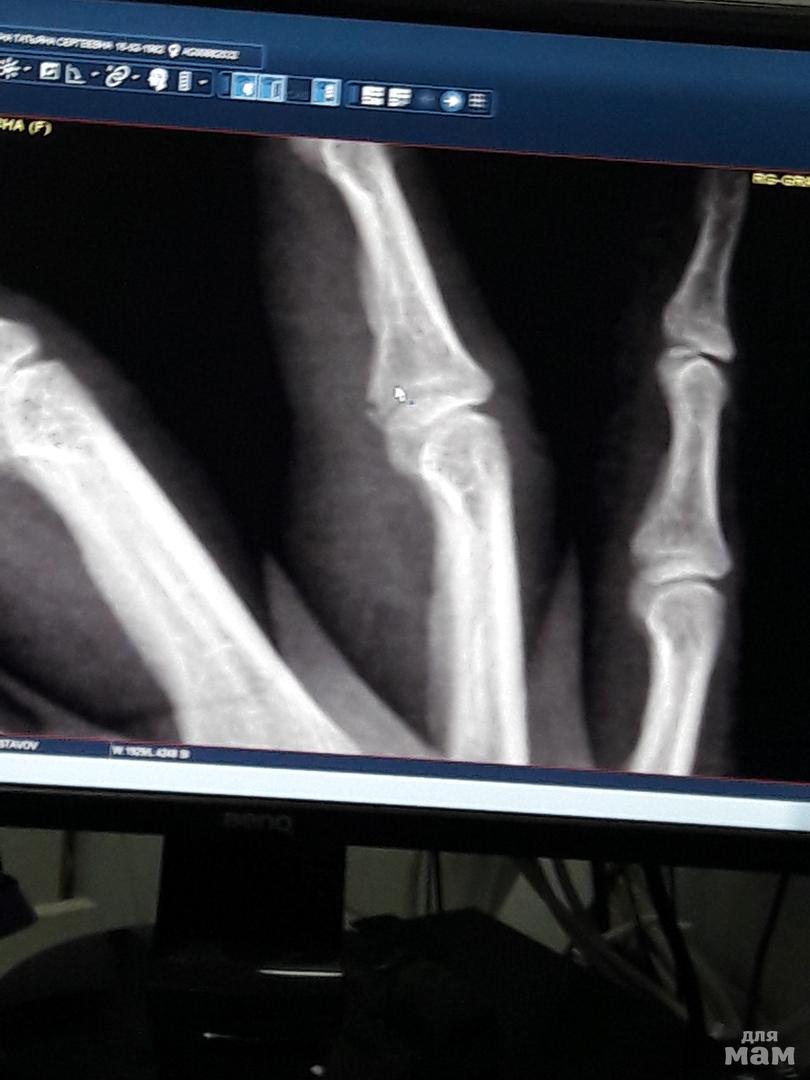

Все это действо мы смотрели на телевизорах, а потом и на чужих планшетах, в центре Москвы. АтмосфЭра заряжена на все 100%. Мы пошли гулять, но вскоре муж с дочерью учесали домой, а меня оставили насладиться одиночеством в многотысячной толпе) Ох... короче, решила я попинать мяч с мальчишками)) попинала блин! С 178 см да 85 кг шваркнуло об плитку на Арбате 😂 Итог - все тело болит, будто вместо мяча пинали меня😂🤣😂, на ноге (на подъеме) думала что грязь от мяча не отмыла как следует, а это синяк, на ладошках никогда не видела синяки, но они у меня есть! Ну и это... 2 недели гипс, потом разрабатывать пальчик. Болело и опухло два, но осколок отвалился на одном. Мой первый и надеюсь последний перелом-трещина.